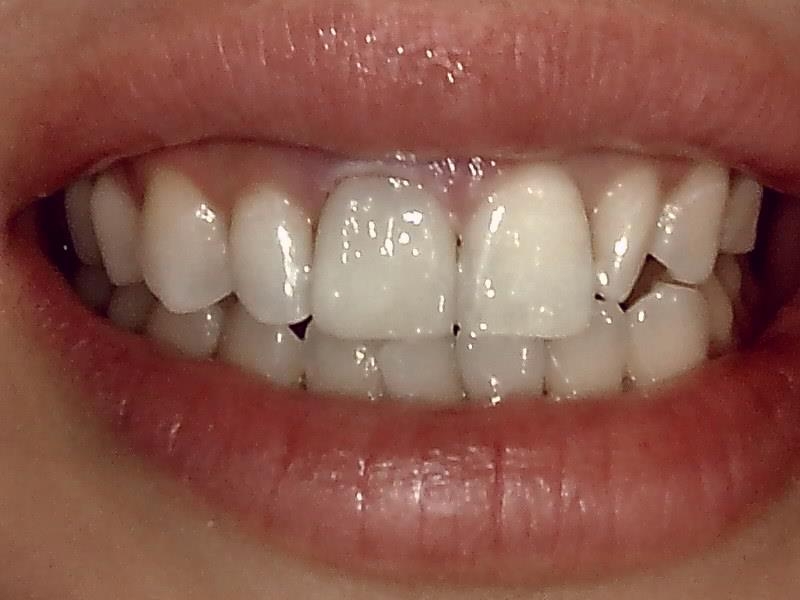

20代後半の女性の審美補綴の症例です。

完成

治癒